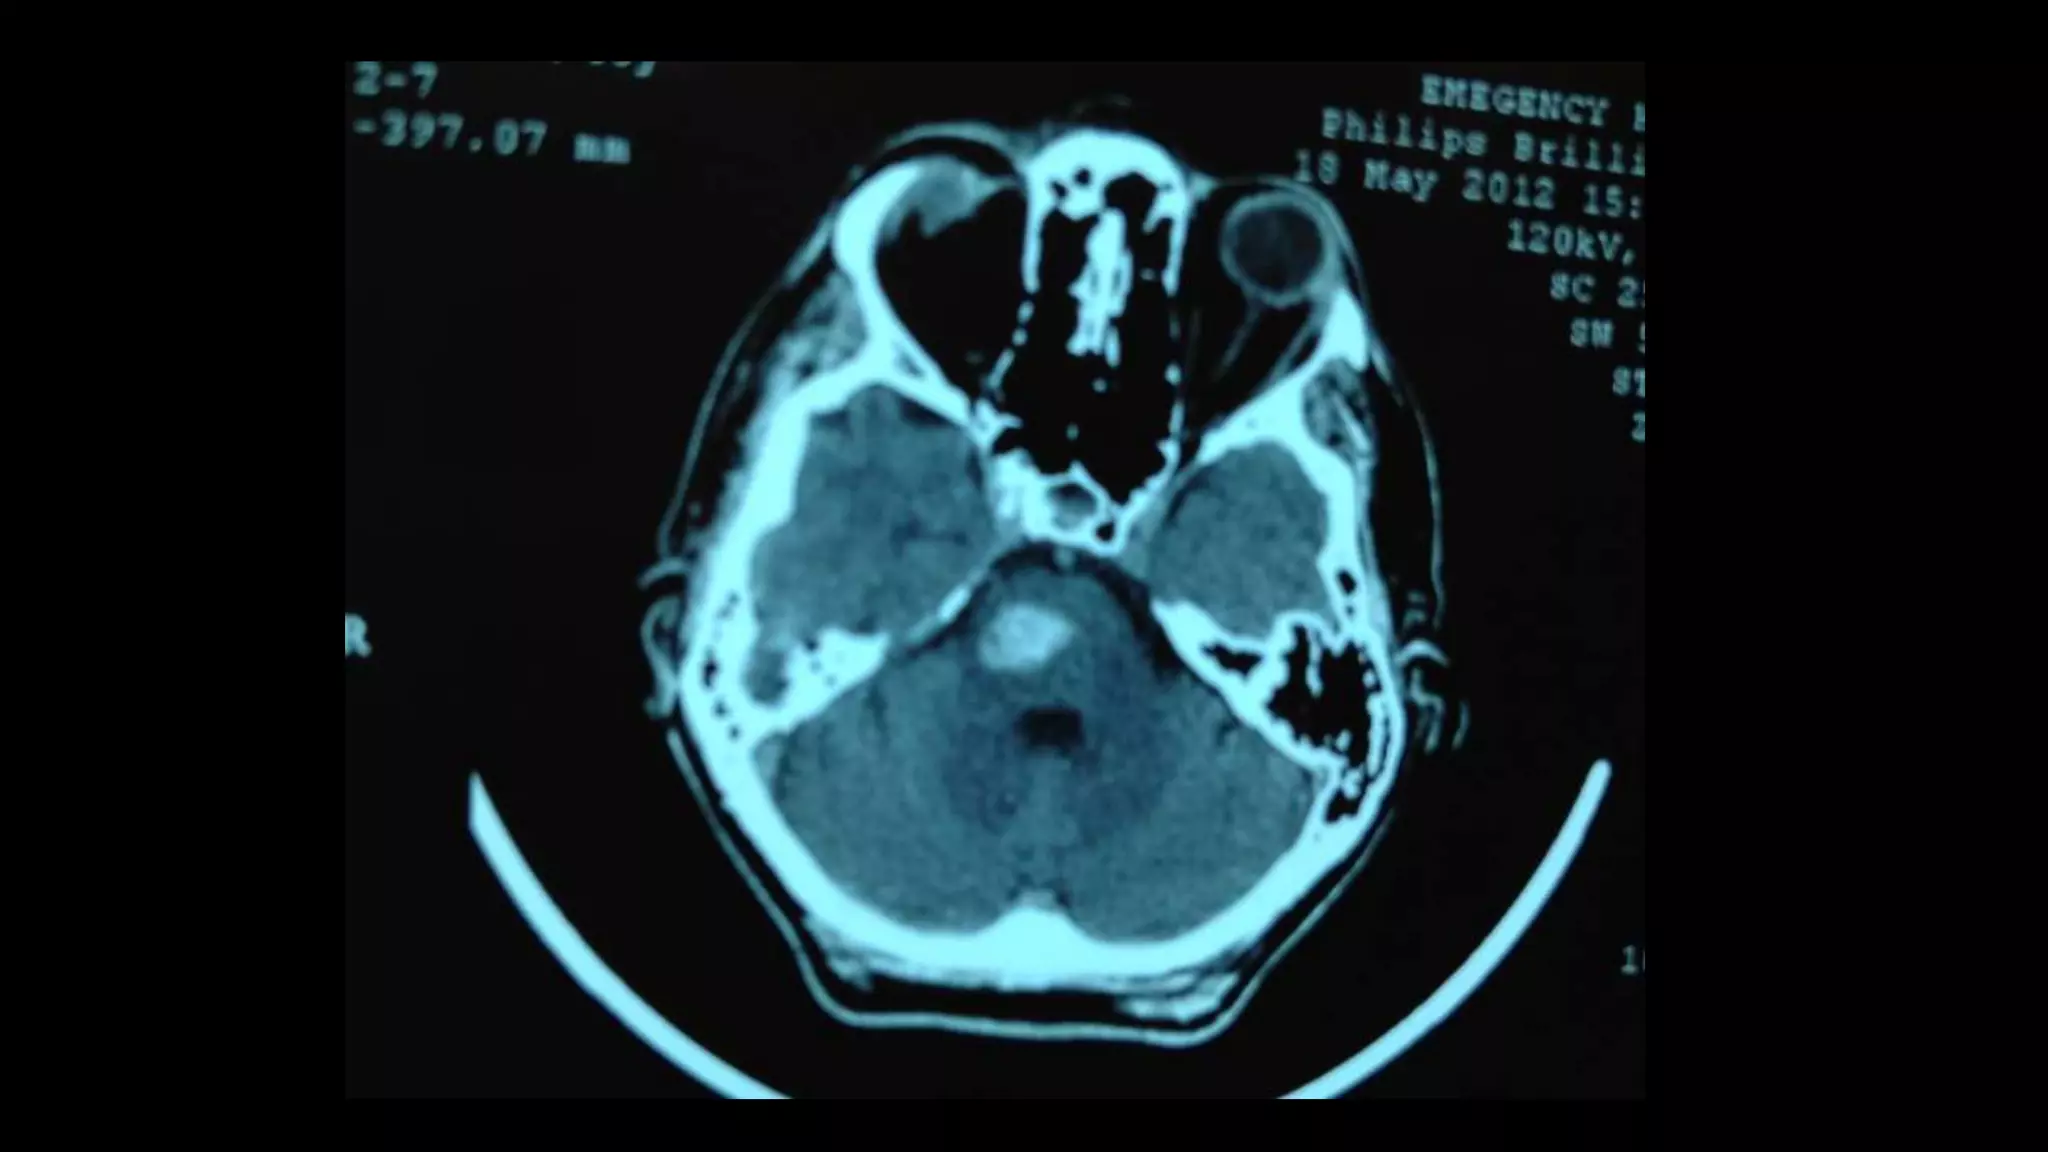

Quadriparesis: brain/high cervical cord MRI, with or

without contrast. Brain CT scan can also be used in the

acute setting; depending on the etiology, it may reveal

a diagnosis, e.g., pontine hemorrhage.